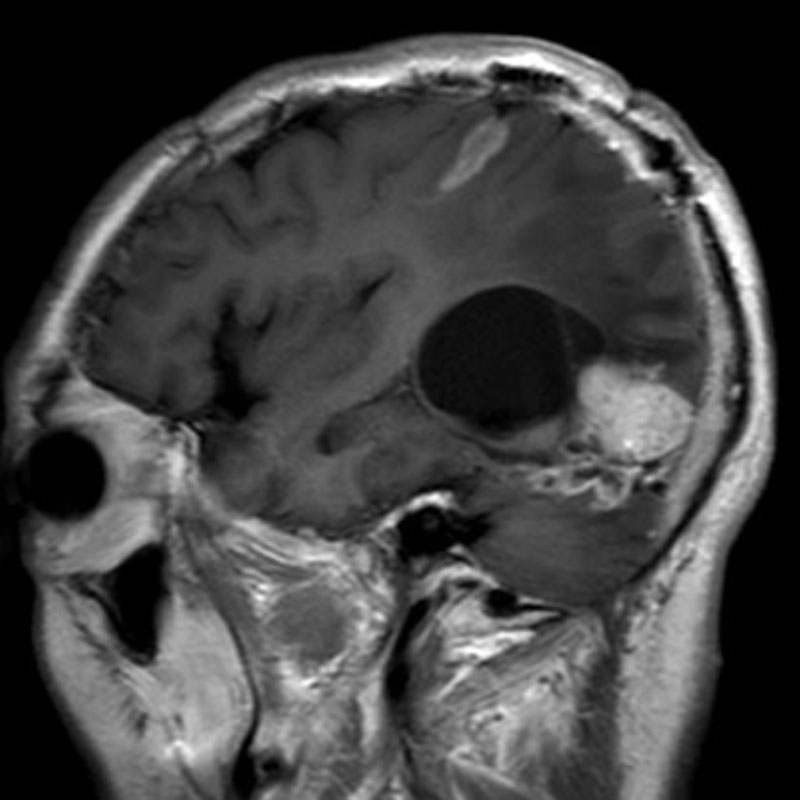

285

'22年4月

70代

膠芽腫

頭蓋内腫瘍摘出術

No.’22_42 手術前1

No.’22_42 手術前2